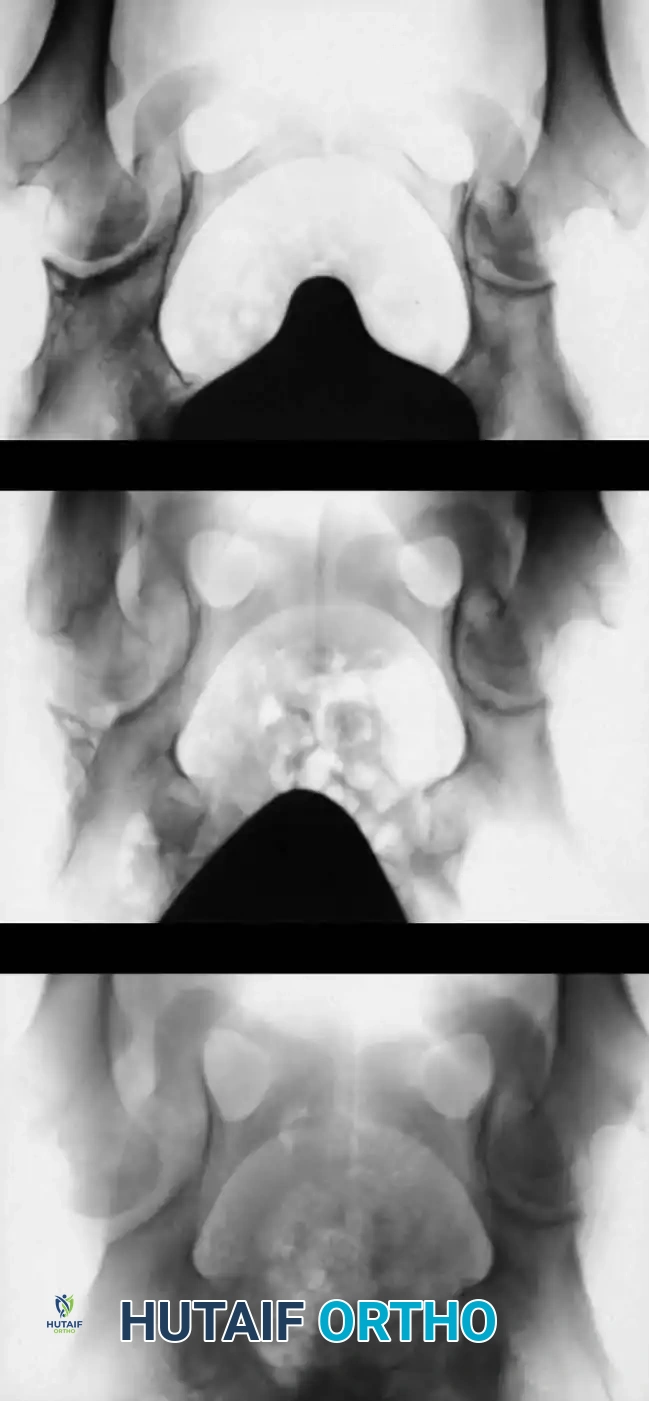

Radiographic appearance following a complex pelvic osteotomy with internal fixation, demonstrating improved center-edge angle and acetabular coverage.

Child (3 to 8 Years): Pelvic and Femoral Osteotomies

In older children, the remodeling potential of the acetabulum diminishes rapidly. Open reduction alone is insufficient; it must be combined with bony procedures to provide mechanical stability and stimulate remodeling.

Femoral Shortening Osteotomy:

In high dislocations, pulling the femur down to the acetabulum creates massive compressive forces, leading to AVN. A subtrochanteric shortening and derotation osteotomy decompresses the joint, allowing reduction without tension.

Pelvic Osteotomies: